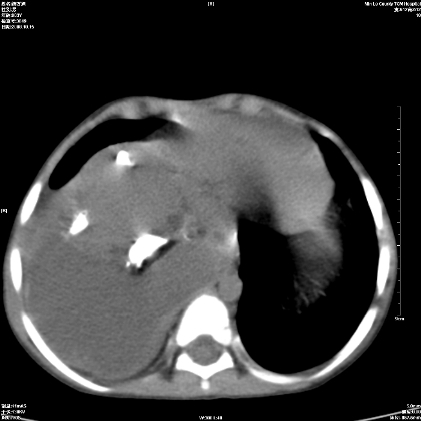

标题: PED1609:男性,3岁。彩超示肝Ca. [打印本页]

标题: PED1609:男性,3岁。彩超示肝Ca.

考虑后纵隔恶性畸胎瘤伴肝内多发转移可能性大,右侧肾上腺转移不除外.

3岁;肝低密度灶;有钙化;有转移灶;考虑肝母细胞瘤;查afp

支持肝母细胞瘤肝内转移

考虑神经母细胞瘤并肝转移